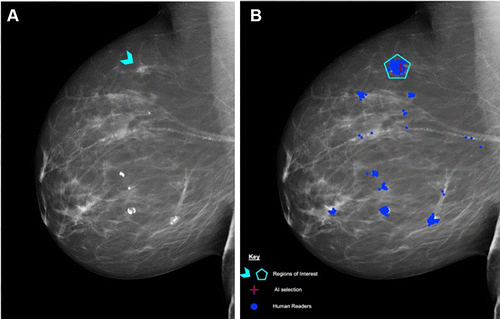

图 3:医生与 AI 对乳腺 X 光片的分析结果

A:蓝色箭头为直径 8 mm 的不明肿块,后鉴定为组织学 2 级导管癌;

B:红色十字是 AI 发现的异常特征,蓝点是医生在分析时标注出的可疑区域。